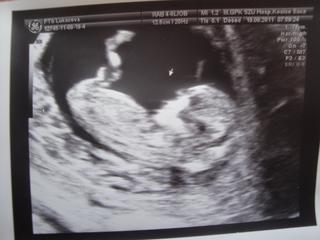

@zlatulienka xixi tiez som sa pobavila 😵 na ultrazvuku vidno ciarocku v podbrusku a podla jej sklonu je to chlapcek alebo dievcatko, tak nejako laicky nam to lekar vysvetloval 🙂 my cakame chlapceka 🙂 fotka je z 12tt

@janka273 Janulík, aj ja mám fotku v skutočnosti omnoho ostrejšiu, nevedela som ako to dostať do PC, skener doma nemám, tak som to odfotila mobilom, asi preto je to také rozmazané 😖